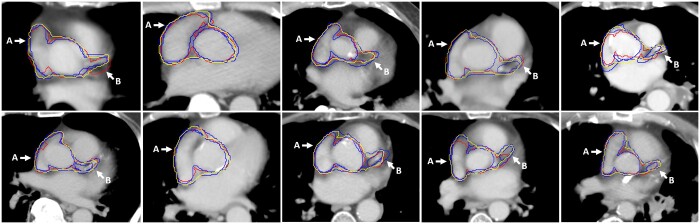

Objectives: We validated an auto-contouring algorithm for heart substructures in lung cancer patients, aiming to establish its accuracy and reliability for radiotherapy (RT) planning. We focus on contouring an amalgamated set of subregions in the base of the heart considered to be a new organ at risk, the cardiac avoidance area (CAA), to enable maximum dose limit implementation in lung RT planning.

Methods: The study validates a deep-learning model specifically adapted for auto-contouring the CAA (which includes the right atrium, aortic valve root, and proximal segments of the left and right coronary arteries). Geometric, dosimetric, quantitative, and qualitative validation measures are reported. Comparison with manual contours, including assessment of interobserver variability, and robustness testing over 198 cases are also conducted.

Results: Geometric validation shows that auto-contouring performance lies within the expected range of manual observer variability despite being slightly poorer than the average of manual observers (mean surface distance for CAA of 1.6 vs 1.2 mm, dice similarity coefficient of 0.86 vs 0.88). Dosimetric validation demonstrates consistency between plans optimized using auto-contours and manual contours. Robustness testing confirms acceptable contours in all cases, with 80% rated as "Good" and the remaining 20% as "Useful."

Conclusions: The auto-contouring algorithm for heart substructures in lung cancer patients demonstrates acceptable and comparable performance to human observers.